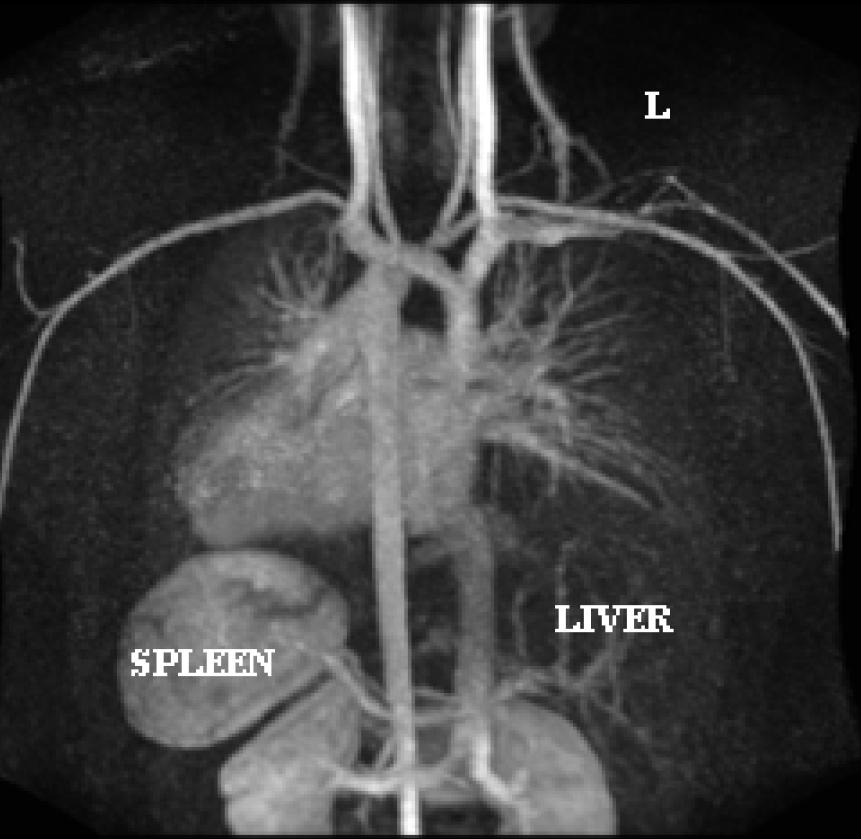

Figure 2